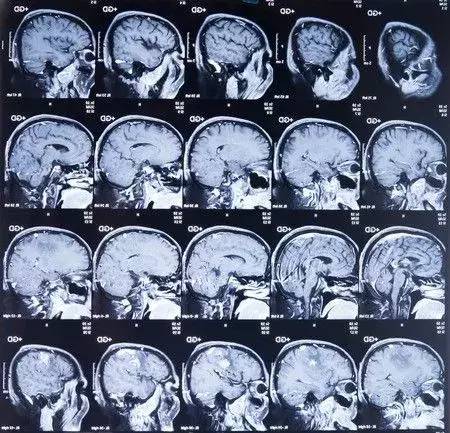

3、核磁共振(MRI): 中文全稱磁共振成像,利用原子核自旋運動的特點,在外加磁場內,經射頻脈沖激后產生信號,用探測器檢測并輸入計算機,并轉換成圖像。

一般對于脊柱的疾病,我們首先進行X光片的檢查,畢竟X光片造價比較低。但是如果我們想看看自己有沒有椎間盤突出,是否壓迫到了神經,那最好的方式就是拍個核磁。因為間盤、神經都屬于軟性的組織,核磁看的最清楚。但是如果是想看看有沒有椎體滑脫還是應該拍X光片。如果懷疑有脊柱腫瘤、結核,那最好的方式就是拍CT。 “